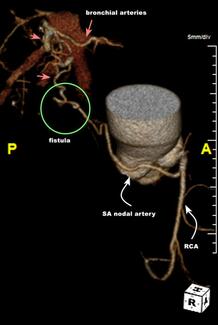

The authors present a 67-year-old male with past medical history of hyperlipidemia, hypertension, and emphysema, and who was a former smoker, with dyspnea on exertion and chest pain.

The authors present a...